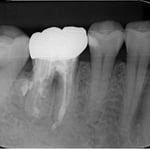

他院で抜歯と診断された症例です。友人の歯科医師の紹介で遠方から通院されました。初診時(左図)には、楔印で示すように、歯の根の先に黒い影が明瞭に写っています。が治療開始から8ケ月後(右図)では、黒い影は消えたり縮小しています。

歯の根の先の黒い影も消え(左図)、(手前は完全に消えていないが、完全な縮小傾向と症状がない)たので、クラウンを装着するための型採りをします。

右図の楔印は破折線です。破折線は特殊な方法で修復しています。

治療期間:約1年

治療回数:10回(1回/月)

治療費:29万円(根管治療+支台築造+セラミックス・クラウン)※毎回の処置料は別途

治療のリスク:他院では再治療ができないこと。

※リスクはどのような治療にも必ずあること。